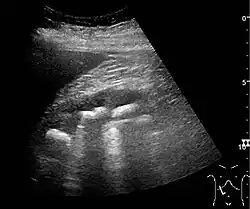

The kidney is divided into parenchyma and renal sinus. The renal sinus is hyperechoic and is composed of calyces, the renal pelvis, fat and the major intrarenal vessels. In the normal kidney, the urinary collecting system in the renal sinus is not visible, but it creates a heteroechoic appearance with the interposed fat and vessels. The parenchyma is more hypoechoic and homogenous and is divided into the outermost cortex and the innermost and slightly less echogenic medullary pyramids. Between the pyramids are the cortical infoldings, called columns of Bertin (Figure 1). In the pediatric patient, it is easier to differentiate the hypoechoic medullar pyramids from the more echogenic peripheral zone of the cortex in the parenchyma rim, as well as the columns of Bertin (Figure 2).[1]

Figure 2. Normal pediatric kidney. * Column of Bertin; ** pyramid; *** cortex; **** sinus.[1] -